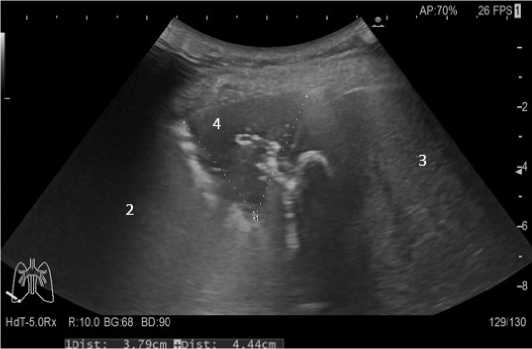

Рисунок 2. Ультразвуковое исследование в В-режиме: 1, 2 – утолщенная диафрагма в области реберно-диафрагмального синуса; 3 – правая плевральная полость. Дефект диафрагмы (отмечено желтой стрелкой). Линейная гиперэхогенная структура в правом подпеченочном пространстве с эффектом массивной акустической тени (отмечено белыми стрелками)

Figure 2. B-mode ultrasound: 1, 2 – thickened diaphragm in the area of the costophrenic sinus; 3 – right pleural cavity. Diaphragm defect 1(marked with a yellow arrow). Linear hyperechoic structure in the right subhepatic space with the effect of a massive acoustic shadow (marced with white arrows)

Рисунок 3. Ультразвуковое исследование в В-режиме: 1 – ре берно-диафрагмальный синус (отмечено курсором); 2 – ткань нижней доли правого легкого с признаками гиповентиляции; 3 – паренхима печени; 4 – отграниченное жидкостное скопление с неоднородным содержимым в правой плевральной полости Figure 3. B-mode ultrasound: 1 – costophrenic sinus (marked with a cursor); 2 – tissue of the lower lobe of the right lung with signs of hypoventilation; 3 – liver parenchyma; 4 – limited fluid accumulation with hetergeneous contents in the right pleural cavity